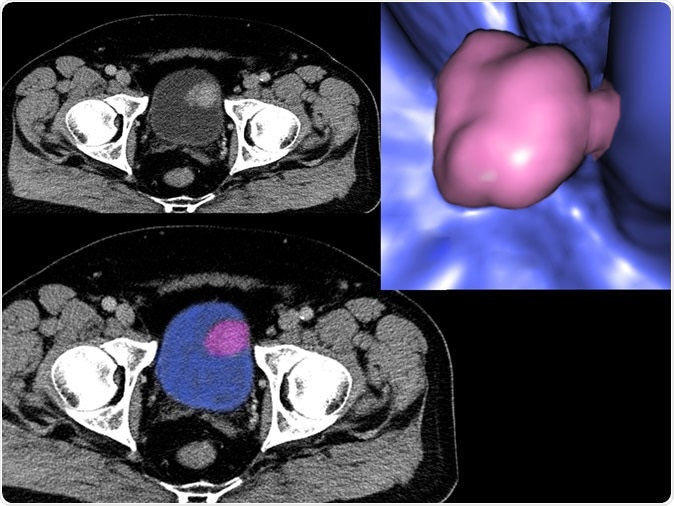

Bladder cancer, CT - Illustration Credit: Semnic / Shutterstock